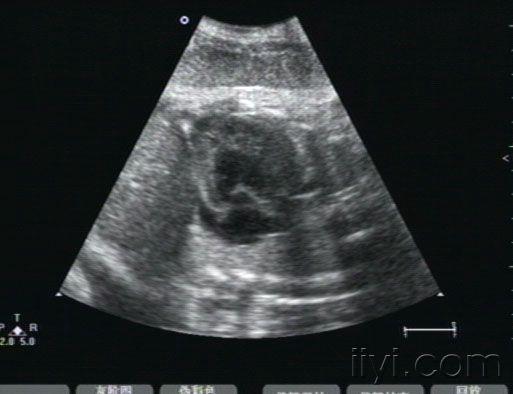

胎儿心包积液

• 孕38周,10天以前在多家医院检查胎儿正常。近一周来自觉腹胀,下坠。发现胎儿心包积液,并且右室壁好象很厚。胎儿生下来后,临床医生没有听到杂音,遗憾的是孩子也没来检查心脏。我们没有开展胎儿心脏,请各位专家帮忙看下,到底是什么原因,胎儿右室壁增厚考虑什么病,为什么生后没有杂音呢?